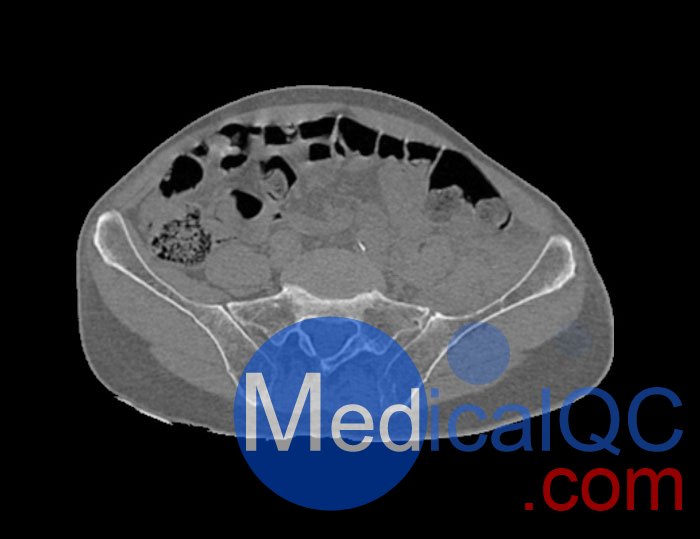

左側(cè)股骨頸移位骨折。

診斷特征

骨骼和軟組織的逼真模擬。

WEK54-01股骨頸骨折骨盆模型,WEK54-01骨盆模體成像效果圖: